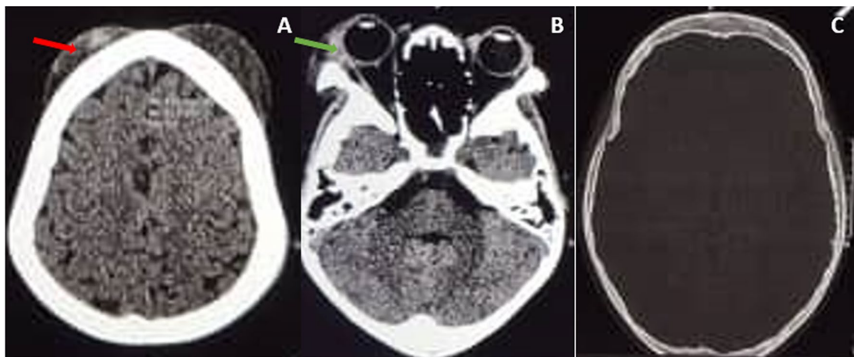

来自乌干达的研究团队在《Journal of Medical Case Reports》报道了一例极具教学意义的病例:一名未接受羟基脲治疗的9岁SCD男性患儿,突发多发性头皮血肿并迅速进展为右眼OCS,伴随中性粒细胞增多的轻度贫血(血红蛋白8.9 g/dL)。通过非增强头颅CT确诊为双侧额部帽状腱膜下血肿合并右眼眶受累,关键影像显示血肿最大达7×7 cm但无颅骨侵犯

研究采用的核心技术包括:1)CT影像学评估(排除颅骨骨折及硬膜外血肿);2)眼科全套检查(角膜荧光染色、眼压测量及眼底镜检查);3)血液学监测(全血细胞计数追踪感染迹象)。这些手段在资源有限地区具有较高可行性。

患儿表现为4处波动性头皮血肿(最大7×7 cm)伴右眼突眼,角膜下1/3荧光染色阳性但视力未受损。与创伤性血肿的关键区别在于无外伤史及CT显示的特征性骨髓腔扩张。

ASHS的发病机制被推测与镰状红细胞诱发颅骨骨髓梗死、皮质破坏相关。团队强调避免穿刺的重要性——既防止感染,也避免引发法律纠纷。OCS管理中的创新点在于采用简易眼罩联合抗生素眼膏,有效预防了角膜溃疡导致的永久性视力损伤。